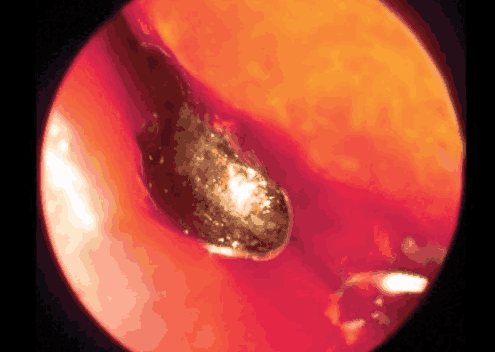

Hình ảnh nội soi cho thấy viên kẹo bị mắc kẹt trong mũi bé gái.

Bác sĩ cho biết trong mũi trái của bé có dị vật kích thước nhỏ là một viên kẹo.

Tình trạng này kéo dài một tuần, khi không thấy dấu hiệu chuyển biến bà mẹ trẻ mới sốt sắng đưa con tới bệnh viện kiểm tra. Tại đây, bác sĩ chẩn đoán mũi trái của bé có dị vật kích thước nhỏ, vì mắc kẹt lâu ngày nên mũi bắt đầu có tình trạng viêm loét nếu không phẫu thuật ngay sẽ rất nguy hiểm.

Rất may ca phẫu thuật sau đó diễn ra thuận lợi, khi được bác sĩ cho xem dị vật từ mũi con gái, người mẹ “đứng hình” vì biết đó là một viên kẹo. Cô thừa nhận bản thân sơ suất không để mắt kỹ càng tới con nên bé gặp nạn như vậy.